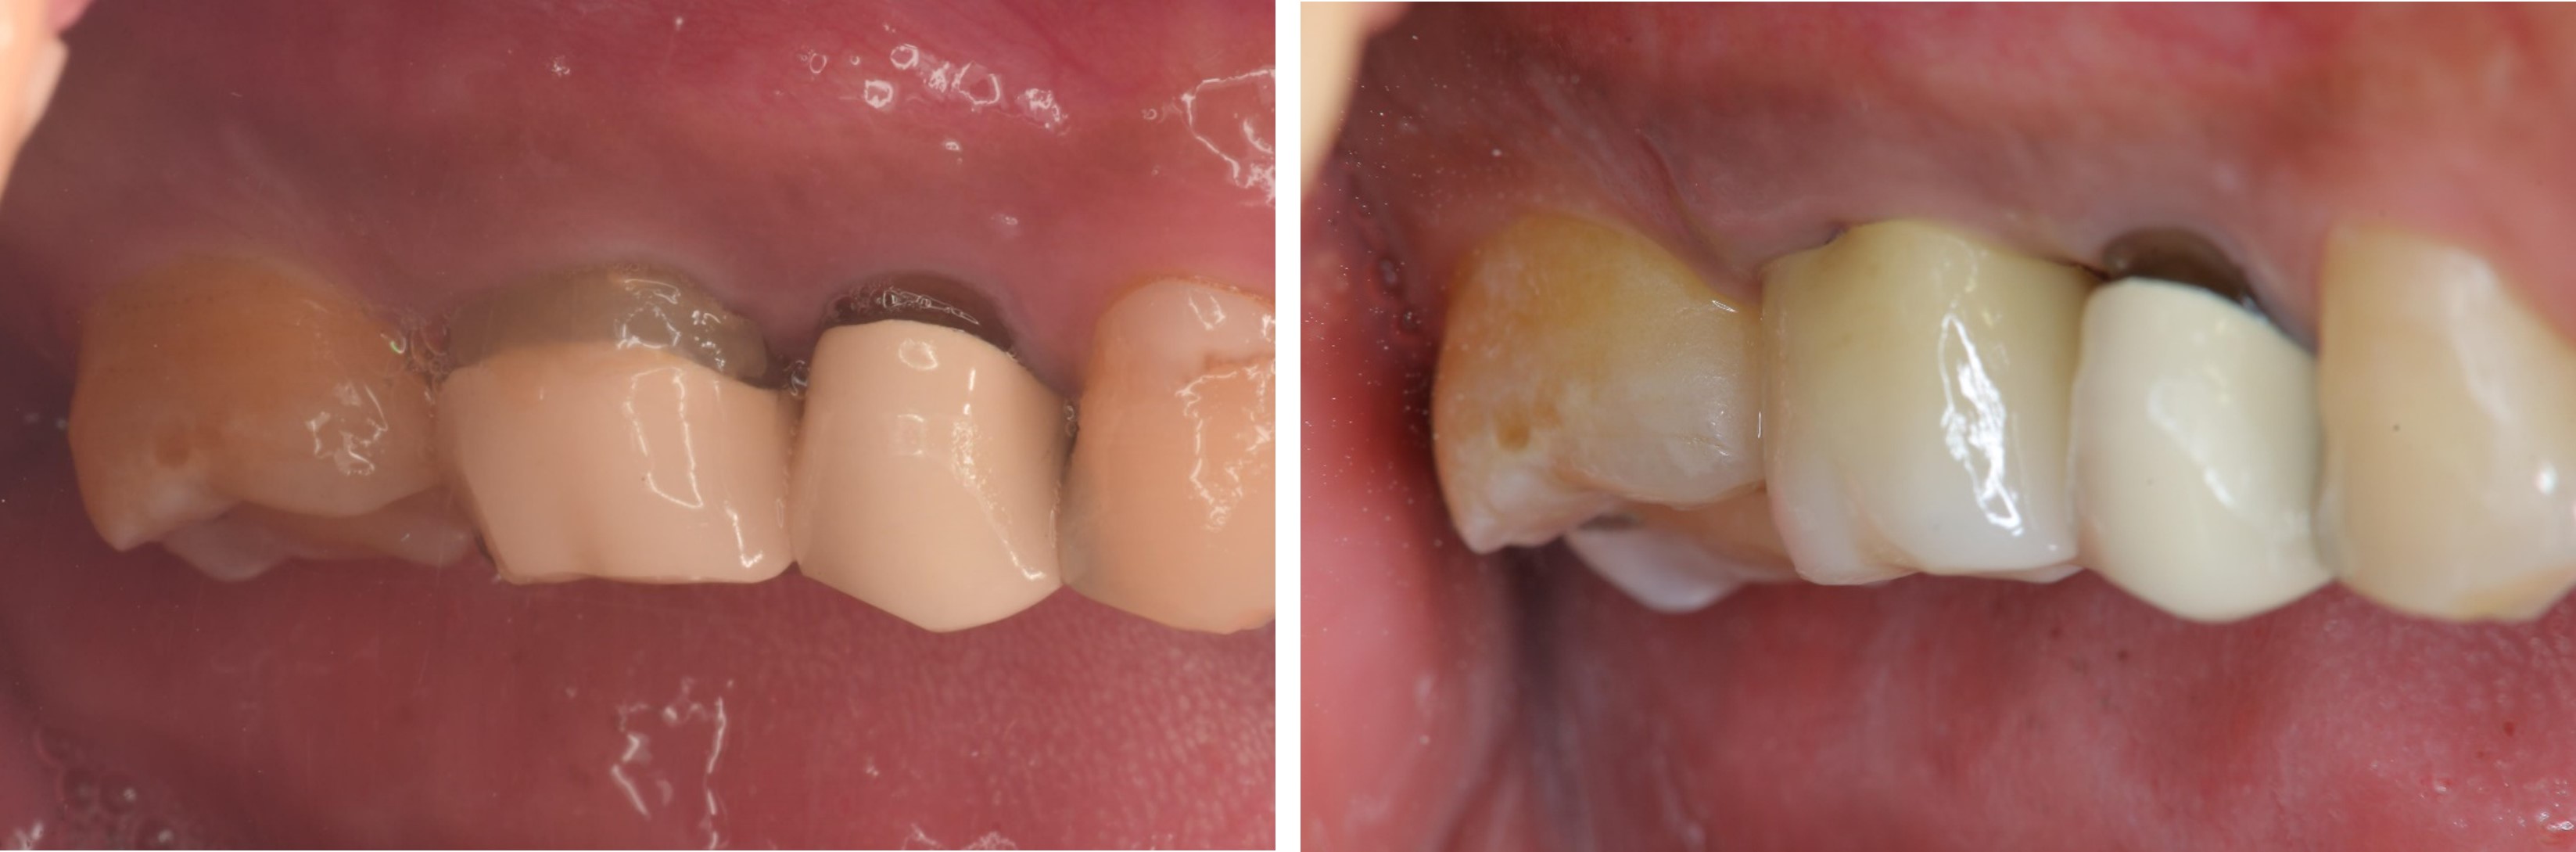

術前、術後比較